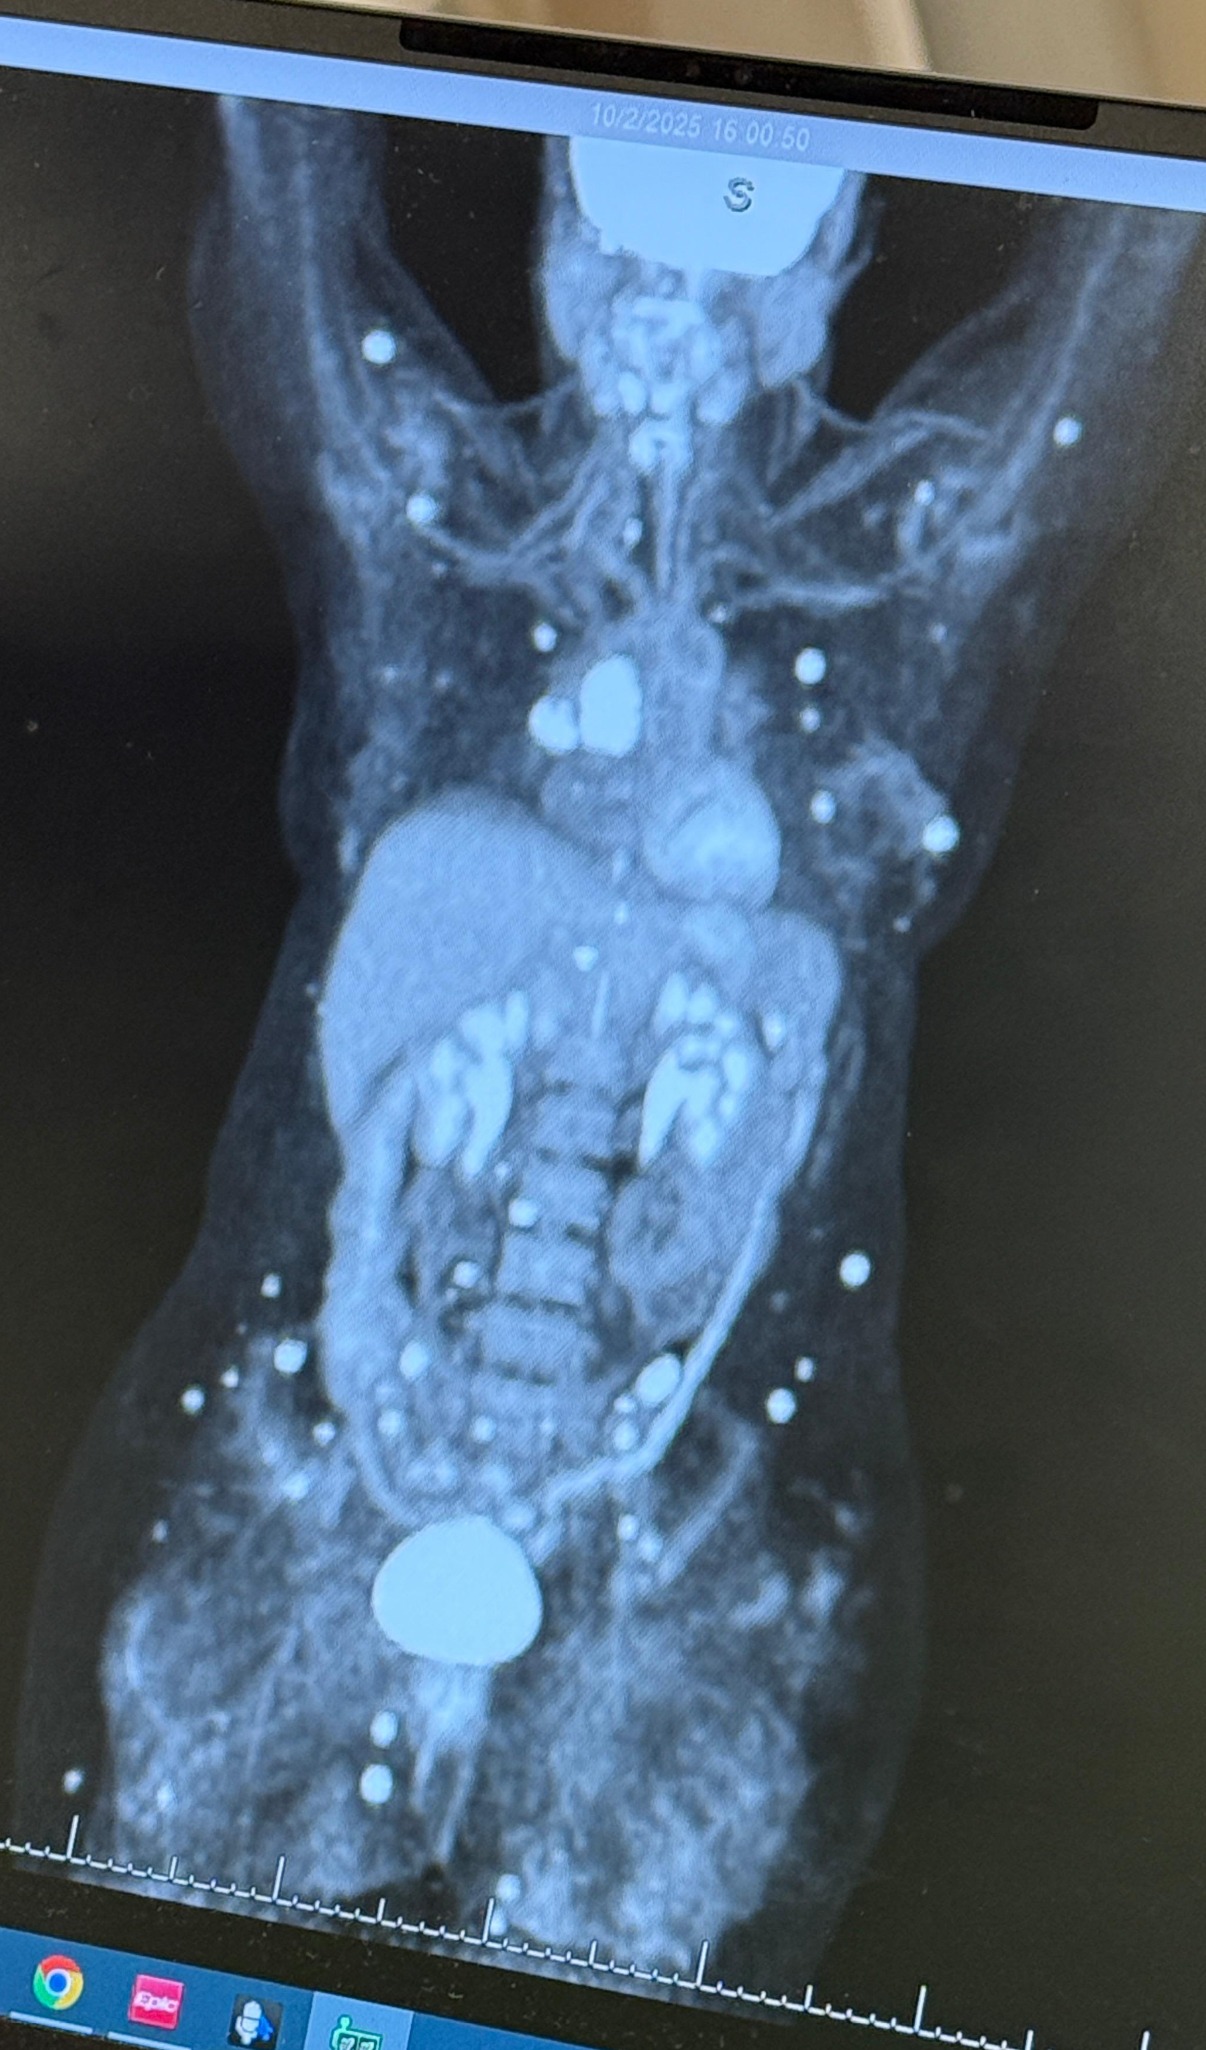

Y hoy, nuevamente, la vida nos presenta otro reto: el cáncer ha regresado, esta vez con metástasis en ganglios linfáticos, músculos, órganos y huesos, lo que lo clasifica como un estadio 4. Los médicos están haciendo todo lo posible con tratamientos y cuidados; ellos dicen que es tratable, aunque no curable. Pero nosotros creemos que Dios es nuestro sanador, y que mientras haya vida, hay propósito.

And now, life has presented us with another challenge: the cancer has returned, this time with metastasis to lymph nodes, muscles, organs, and bones, which classifies it as stage 4. The doctors are doing everything possible through treatments and care; they say it is treatable, though not curable. But we believe that God is our healer, and that as long as there is life, there is purpose.